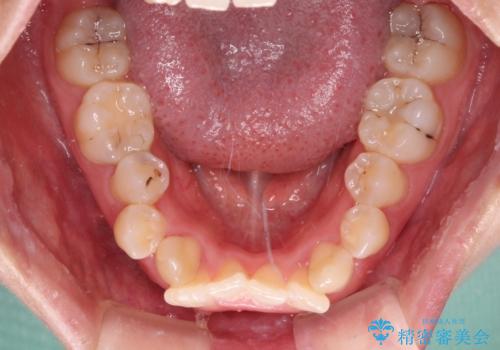

- 上下前歯のデコボコを気にして来院された患者様です。

口元の突出感はあまりなかったものの、デコボコを非抜歯で改善すると出っ歯になる可能性があるため、上下左右の第一小臼歯4本を抜歯し、ワイヤー装置にて矯正治療を行うこととしました。